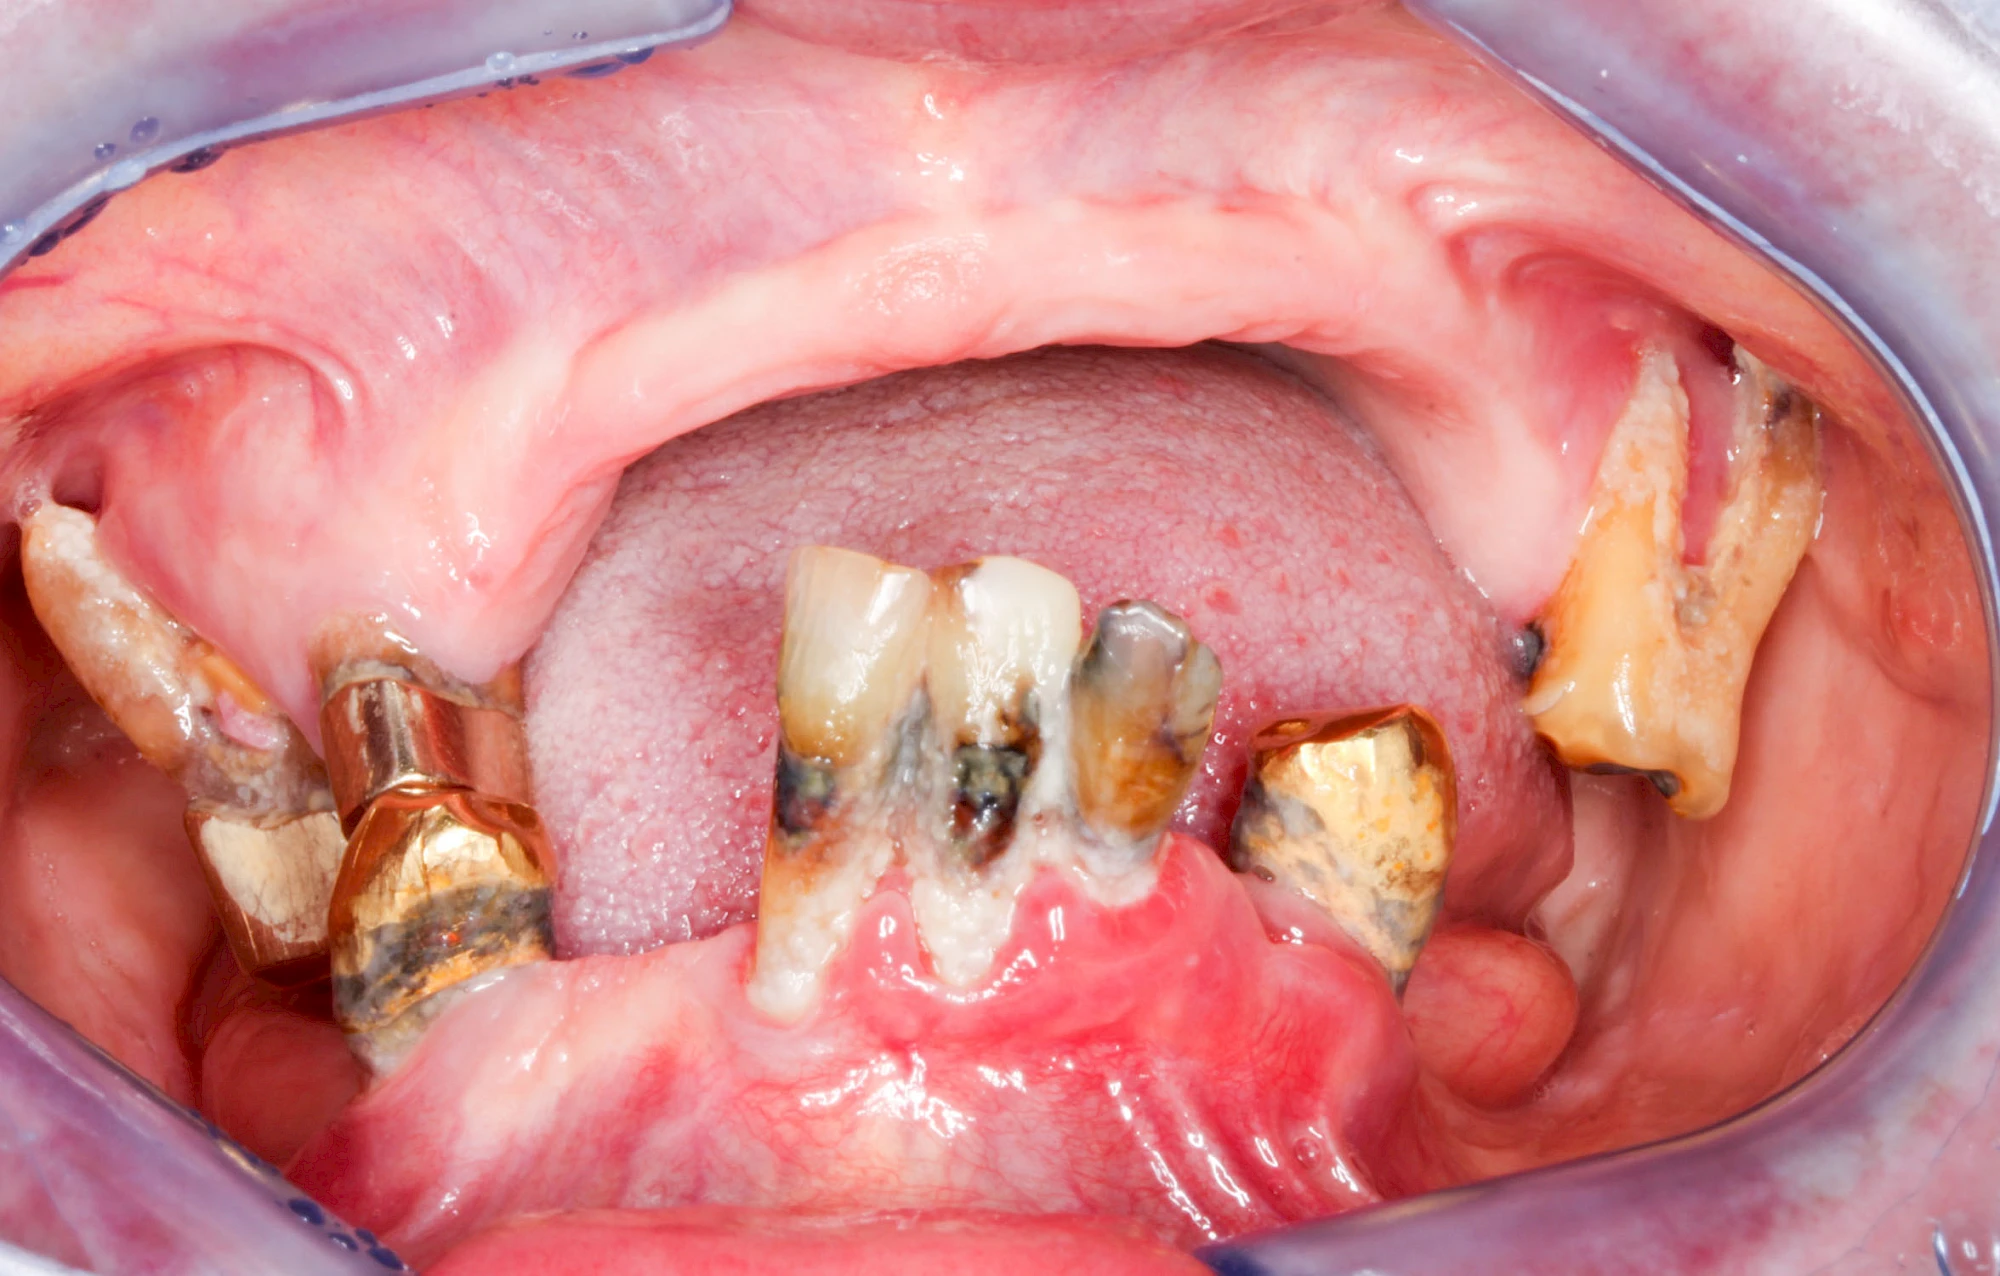

Ist zunächst nur das Zahnfleisch von der Entzündung betroffen, spricht man von Gingivitis. Später, wenn auch der Knochen um die Zähne herum entzündet ist, spricht man von einer Parodontitis. Bei der Parodontitis wird der Knochen nach und nach abgebaut und das Zahnfleisch zieht sich zurück. Die Zahnhälse und Zahnwurzeloberflächen liegen mehr und mehr frei. Die Zähne werden zunehmend lockerer und fallen schließlich aus.

Immunseneszenz & persisitierende Keime

Im Alter lässt die Leistungsfähigkeit des Immunsystems nach. Chronische Erkrankungen nehmen unter anderem durch die ausbleibende Reifung der T-Lymphozyten in Folge der Thymusalterung sowie der gesteigerten Ausschüttung von proinflammatorischen Zytokinen zu. Die vermehrte Freisetzung von Radikalen in den Zellen (oxidativer Stress) hat zudem einen negativen Einfuss auf die Ablesefähigkeit proteincodierter Genabschnitte. Die Folge ist eine sogenannte Dysbiose – eine Gleichgewichtsstörung der bakteriellen Zusammensetzung der Biofilme im menschlichen Organismus und in der Folge kommt es zur Stoffwechselentzündung (Metaflammation). Die individuelle Immunreaktion – so viel ist heute klar – spielt mit die größte Rolle – auch bei der Entwicklung der Parodontitis.